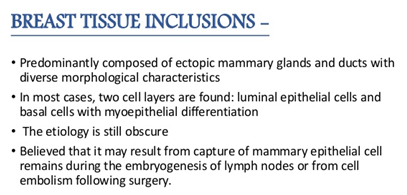

- Lymph node inclusions of mammary gland origin may be composed of deformed mammary gland ducts with divergent morphology and a dual cell population comprising of luminal cuboidal /columnar epithelial cells and basal cells depicting myopithelial differentiation (Figure 1).

- Mammary Inclusions: Axillary lymph nodes may frequently depict the ectopic mammary tissue. Inclusions of the breast tissue are demonstrated as mammary ducts in the subcapsular region. The cellular components described are the epithelium, myoepithelium and apocrine cells. Cystic spaces lined with low, uniform cuboidal epithelium lacking mitosis, hyperplasia or hyperchromasia may be evidenced.4 A singular layer of cuboidal epithelium interlining the tubules (hobnail appearance) or epithelial inclusions situated within or beneath the lymph node capsule may also be elucidated. A distinction is required from a metastatic breast carcinoma. The inclusions may delineate three categories i) glandular structures only ii) squamous cysts only iii) a combination of glandular and squamous epithelium.5

Figure 1 Origin of mammary inclusions